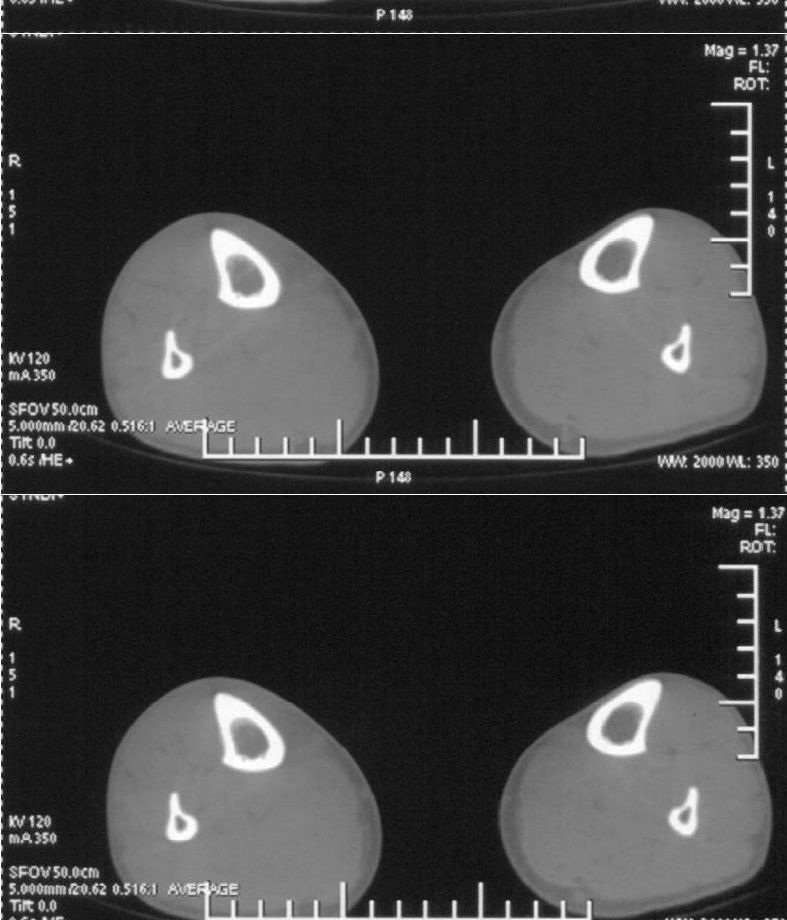

男,42岁。4个月前钢筋钝伤右侧小腿部,当时因无明显外伤,未引起重视。一周后因受伤腿部疼痛,发现肿胀,随后到当地医院进行检查(2008年4月16日)。因未发现骨质异常未引起重视,仅仅进行口服抗生素治疗处理。经过一段时间治疗但未见明显治疗效果在5月29日又进行x线检查,发现有胫骨密度上段密度增高,又进行抗炎治疗,仍未见效果。又在7月3日进行x线检查,仍然报告有胫骨上端密度增高,并建议ct检查。以下是相关检查结果:

髓腔密度呈絮状增高,胫骨上端内侧可见层状骨膜反应,考虑骨髓炎.

髓腔密度呈絮状增高,胫骨上端内侧可见层状骨膜反应,肌间隙模糊,考虑骨髓炎.